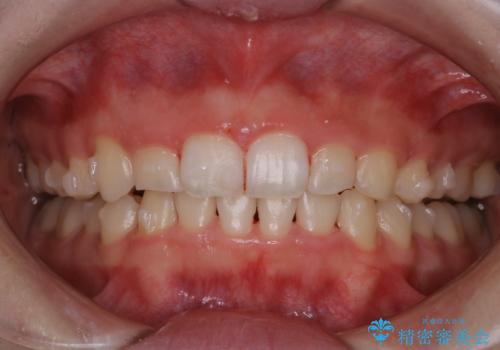

インビザライン中にステインの除去

- インビザラインでのマウスピース矯正中の方で、歯の表面のステインをきれいに取りたいとのことでした。PMTC60分コースを行いました。

PMTC(保険外治療)は、毎日の歯磨きで落としきれない汚れや、コーヒ、紅茶・タバコのヤニなどの着色も除去します。目には見えない歯と歯の間・歯肉の境目・インビザライン中はアタッチメント周囲などに残っているプラーク(歯垢)もしっかり取り除きます。PMTCでは専門的な機械や材料を使用して、徹底的に汚れを除去するため、虫歯・歯周病・口臭予防などにつながります。

またPMTCを行うことで、ご自身本来の歯の色になり自然な明るさになります。